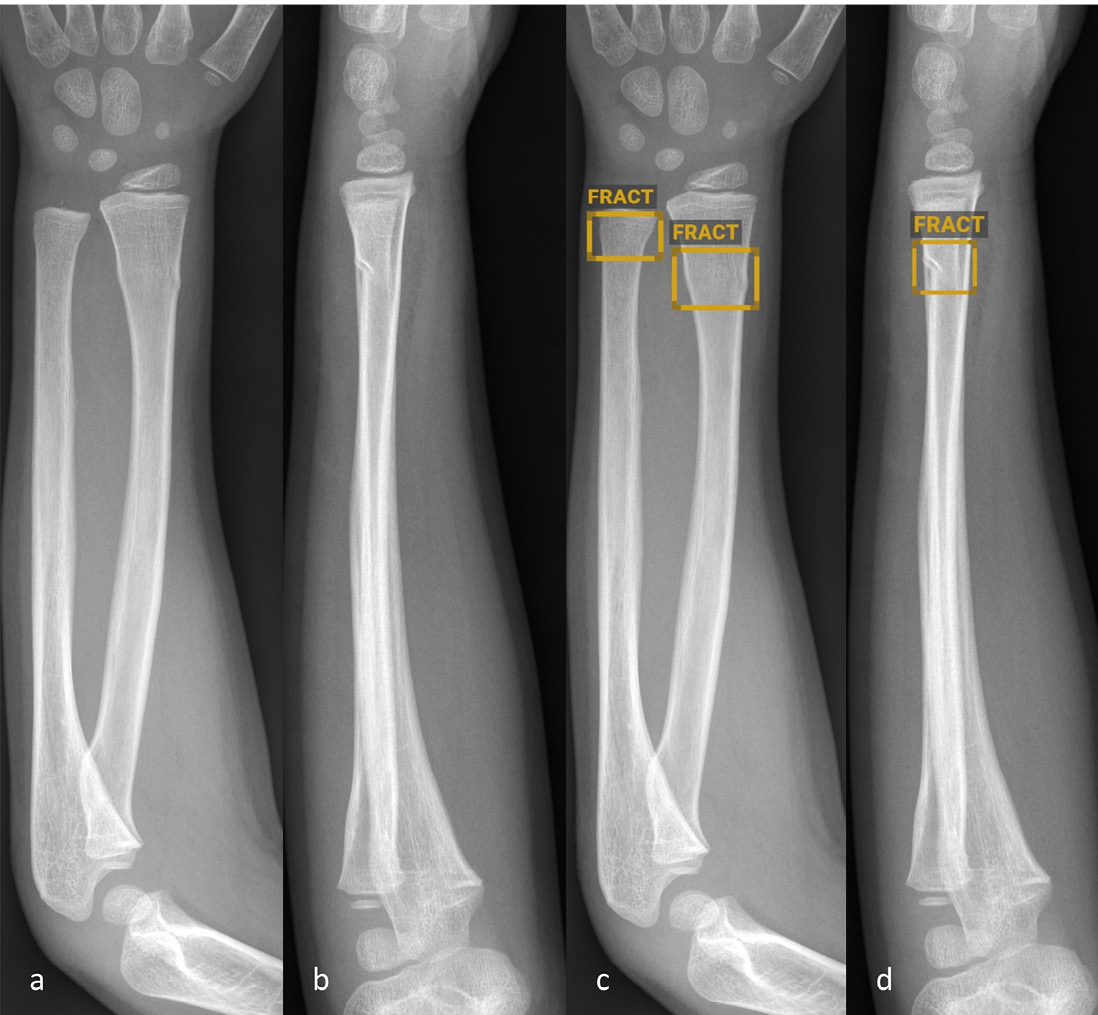

Abbildung 2: Anteroposteriore (a und c) sowie seitliche (b und d) Röntgenbilder des Ellbogens eines sechsjährigen Kindes ohne (a–b) und mit (c–d) Befundmarkierung durch BoneView.

Abbildung 2: Anteroposteriore (a und c) sowie seitliche (b und d) Röntgenbilder des Ellbogens eines sechsjährigen Kindes ohne (a–b) und mit (c–d) Befundmarkierung durch BoneView. Die KI-Software hat die proximale Ulnafraktur korrekt identifiziert und markiert, die Radiusluxation im Rahmen der Monteggia-Luxationsfraktur jedoch nicht erkannt (roter Rahmen, c–d).

© Altmann-Schneider I, Kellenberger CJ, Pistorius SM, Saladin C, et al. Artificial intelligence-based detection of paediatric appendicular skeletal fractures: performance and limitations for common fracture types and locations. Pediatr Radiol. 2024; 54(1):136–145. http://creativecommons.org/licenses/by/4.0/ Die Abbildung entspricht einem Teil des Originals ohne sonstige Veränderung.

Insgesamt gibt es vergleichsweise wenig publizierte Studien zur Fraktur­diagnostik durch KI bei Kindern und Jugendlichen. Die wenigen durchgeführten externen Validierungsstudien der oben beschriebenen kommerziell erhältlichen Soft­wares zeigen durchweg relativ hohe Sensitivitäten und Spezi­fi­täten (mehrheitlich über 90 %) der jeweils getesteten Softwares [4–6]. Die Studien variieren jedoch stark bezüglich Gesamtanzahl analysierter Röntgen­bilder (zwischen 300 und 2634), Anzahl Röntgenbilder pro Altersgruppe sowie Auswertung der Ergebnisse. Nur eine der Studien schlüsselt die Ergebnisse nach spezifischen Frakturtypen auf, lässt dabei aber die anatomische Lokalisa­tion ausser Acht [6]. In einer am Uni­versitäts-Kinderspital Zürich durchge­führten Studie, haben wir kürzlich in einem Datenset von je 1000 Röntgen­bildern häufiger Fraktur­lokalisationen bei Kindern (Vorderarme, Ellbogen und Unterschenkel) die diagnostische Ge­nau­igkeit der KI-Software BoneView (Gleamer) getestet [7]. Für die Gesamt­heit aller Frakturen wurden ähnlich hohe Sensitivitäten und Spez­ifi­täten wie in früheren Publikationen mit derselben Software gefunden [6]. Abbild­ung 1 zeigt ein Beispiel einer von der KI-Soft­ware korrekt identifizierten Torus­­fraktur des Vorderarms. Die Auf­schlüs­selung nach Frakturtyp hat jedoch deutliche Einschränkungen aufgezeigt. So wurden im Bereich der Vorderarme Bie­gung­s­frakturen nicht verlässlich erkannt. Ausserdem war die Detektionsrate für Avulsionen des Processus styloideus ulnae, Torus­frak­turen des proximalen Radius sowie Olekranonfrakturen im Vergleich zu den übrigen Vorder­arm­frakturen deutlich geringer (< 80 %). Im Bereich der Unterschenkel wurden niedrige Detek­tions­raten für «toddler’s fractures» (74 %) und Tram­po­lin­frak­tu­ren (66 %) gefunden. Bei den Ellbogen wurden nur komplette suprakondyläre Frakturen und Radiushalsfrakturen mit einer Detektionsrate über 80 % erkannt. Die Detektion von Gelenkergüssen im Ell­bogen als indirektes Frakturzeichen war nur moderat. Luxationen im Ell­bo­gengelenk wurden nicht verlässlich erkannt (Abbildung 2). Zusammen­fassend lässt sich also festhalten, dass gerade die – zum Teil diskreten, jedoch äusserst relevanten – Befunde, die dem etwas weniger geübten Auge entgehen könnten, auch von der Software nicht verlässlich erkannt werden.